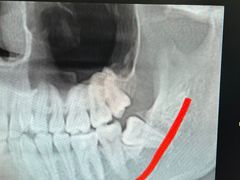

• -牙博士口腔品牌连锁(杨浦店)

无尾熊_4996 | 24-02-02